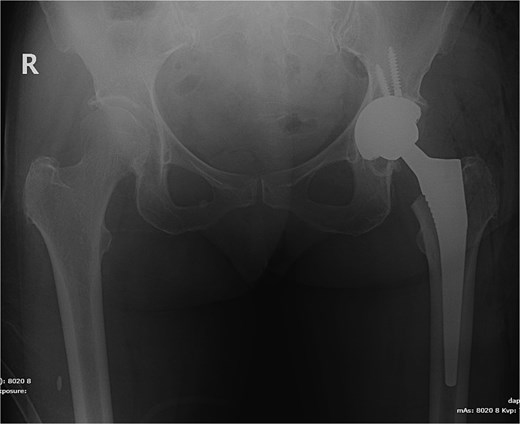

A 77-year-old female comorbid patient presented to the emergency department following a mechanical fall with acute displaced left femoral transcervical fracture (Fig. 1). Laboratory tests showed white blood cell count (WBC) count 11 800, C-reactive protein (CRP) 2.9, erythrocyte sedimentation rate (ESR) 18, and negative urine culture.

X-ray pelvis showing acute displaced and impacted left femoral transcervical fracture.

The patient underwent left total hip arthroplasty (Fig. 2). Her hospital stay was smooth and uneventful without any complications. Her wound was clean and dry without erythema or oozing and was discharged on prophylactic anticoagulation and pain medications.

X-ray pelvis showing left total hip replacement with hardware in adequate position.